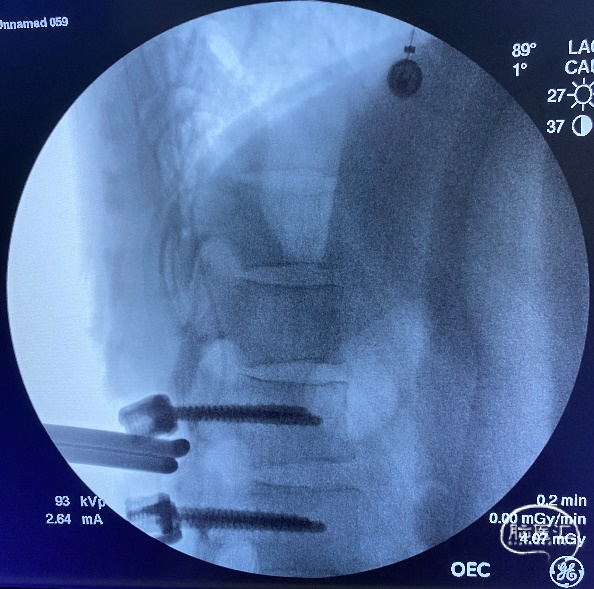

简要手术经过:于肛门括约肌、双侧股四头肌、腓肠肌接电生理监测探针。① 选择后正中入路,充分暴露L1-2棘突及椎板,完成L1-2双侧椎弓根置钉,术中C型臂X线透视确认椎弓根螺钉位置良好(图3)